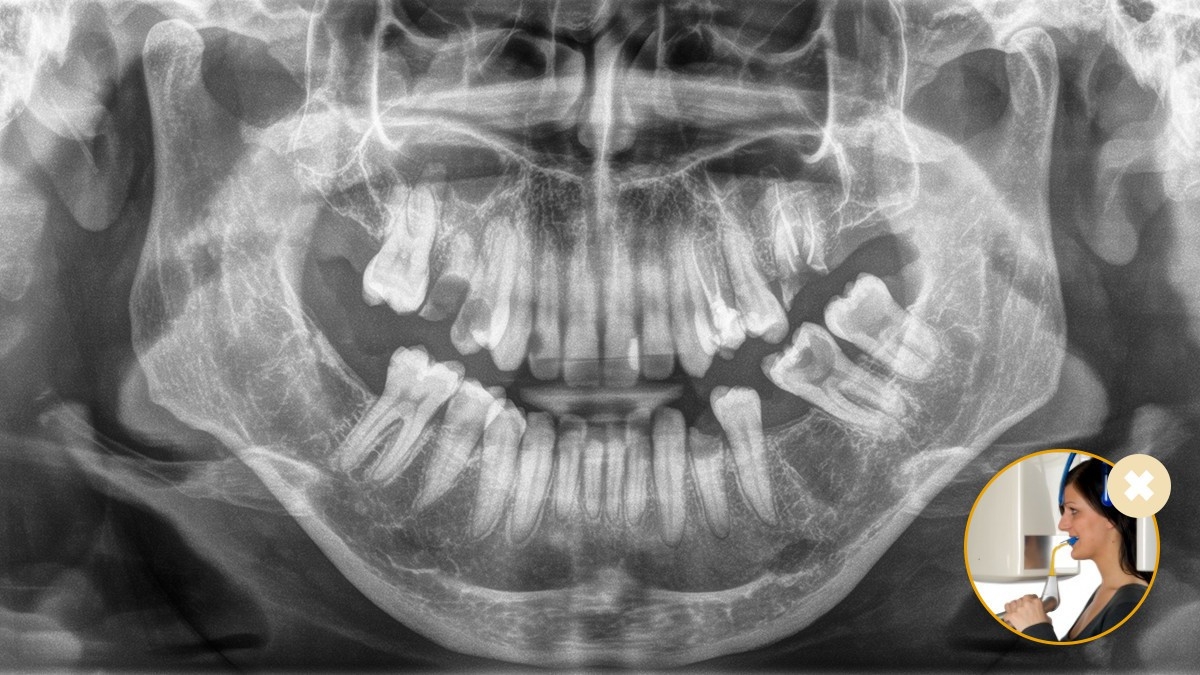

Posicionamiento incorrecto del paciente: paciente inclinado hacia adelante

Posicionamiento incorrecto del paciente: paciente inclinado hacia atrás

Posicionamiento correcto del paciente con el bloqueo de mordida oclusal: inclinación ideal garantizada para imágenes panorámicas.